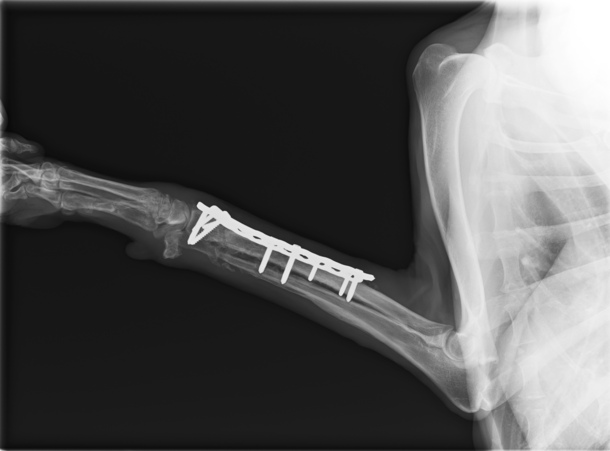

足のレントゲン写真です

1番最近のレントゲン写真です!

真っ白く写る、足先側の洗濯バサミのような器具の形の下あたりが折れた部分なのですが、隙間がほとんどわからないぐらい骨がくっついています!

骨は繋がらないかも…と言われていたので、この結果はとても嬉しいです!ムーンちゃんもご飯をいっぱい食べて頑張ってくれました(^^)

ただ、まだ足先が曲がらず歩く際につま先立ちのようになりフラつくので、リハビリを継続し、お外のお散歩をめざしていきます!